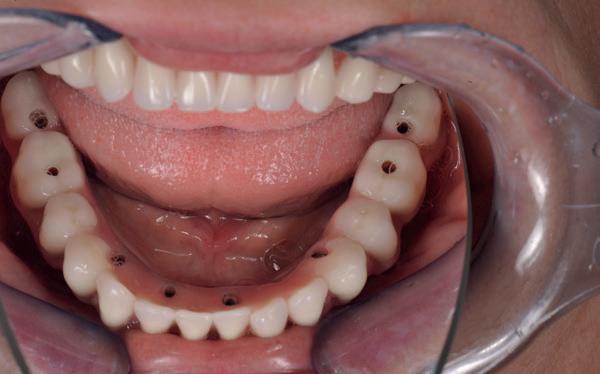

In de prothetische fase (zie foto’s) is in de bovenkaak gebruikgemaakt van verschroefde zirconia bruggen, die enkel buccaal zijn opgebakken. Deze bruggen zijn verlijmd op individuele, geanguleerde titanium abutments. In de onderkaak is een verschroefde kunststofbrug op een titaniumbasis (wrap-around) gemaakt. Voor deze combinatie is gekozen vanwege een minder hinderlijk tikkend geluid bij functie en kleinere kans op breuk van de keramiek. Een nadeel is verhoogde slijtage van de kunststof elementen, maar deze zijn in de jaren later eenvoudig te vervangen op de bestaande brug. Ondanks alle digitale mogelijkheden is de afdruk en registratiefase analoog uitgevoerd, omdat in ervaring van de behandelaren dit bij deze totale rehabilitaties op implantaten nog altijd de grootste precisie oplevert. Er is afgedrukt met impregum in individuele lepels en de pasvorm is gecontroleerd met rigide duralay bars. De relatie wordt vastgelegd zoals bij een volledige prothese met waswallen en pijlpuntregistratie. De opstelling in was wordt gepast en laatste correcties worden gemaakt in samenspraak met de patiënt, de restauratieve tandarts en de tandtechnicus. Na het vastzetten van de suprastructuren worden de schroefgaten afgesloten met composiet.

10. In de bovenkaak is gekozen voor 3 zirconium bruggen; in de onderkaak is gekozen voor een wrap-around met titanium

core.

11. In de bovenkaak is keramiek gebruikt en in de onderkaak kunststof (behandeling is

in de zes maanden bij de mondhygiënist voor peri-implant reiniging, pocketmetingen, mondhygiëne instructies en controles. De AirFlow wordt daarbij standaard gebruikt. Verder wordt de patiënt na één, drie en zes jaar gezien voor controle van de suprastructuren door de restauratieve tandarts. Uit de röntgenfoto’s kan afgeleid worden dat het botniveau gelijk blijft over tijd. Klinisch ziet de situatie er infectievrij uit; de patiënt onderhoudt het zelf netjes met ragertjes, een elektrische tandenborstel als ook de Waterpik.